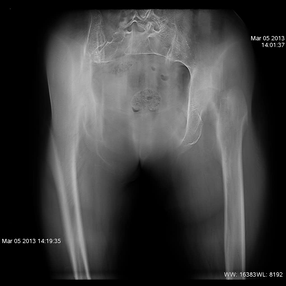

![]() 骨折部分がわかりにくいX線写真

高齢者の股関節は骨粗鬆等により骨折していても単純X線写真では判断しづらい場合があります。

そのような場合、今まではCT室に患者を移してCT検査を行う必要がありましたが、この撮影装置は

単純X線撮影を行った後そのままトモシンセシス(断層)撮影を行えます。

このようにX線撮影室で断層画像を作成できるようになり、救急患者さんの診断に大変役立っています。